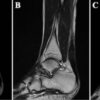

Anatomy-Informed Biomechanics of the Ankle: A 360° Review of Normal and Pathological Function

The ankle is a complex and dynamic joint essential for load transfer, balance, and ambulation. This review presents a 360° exploration of ankle biomechanics by integrating structural anatomy, neuromuscular control, and the biomechanical principles that govern function and dysfunction.

By Dr. Hooman MIR, DPM, MSci, FAPWCA